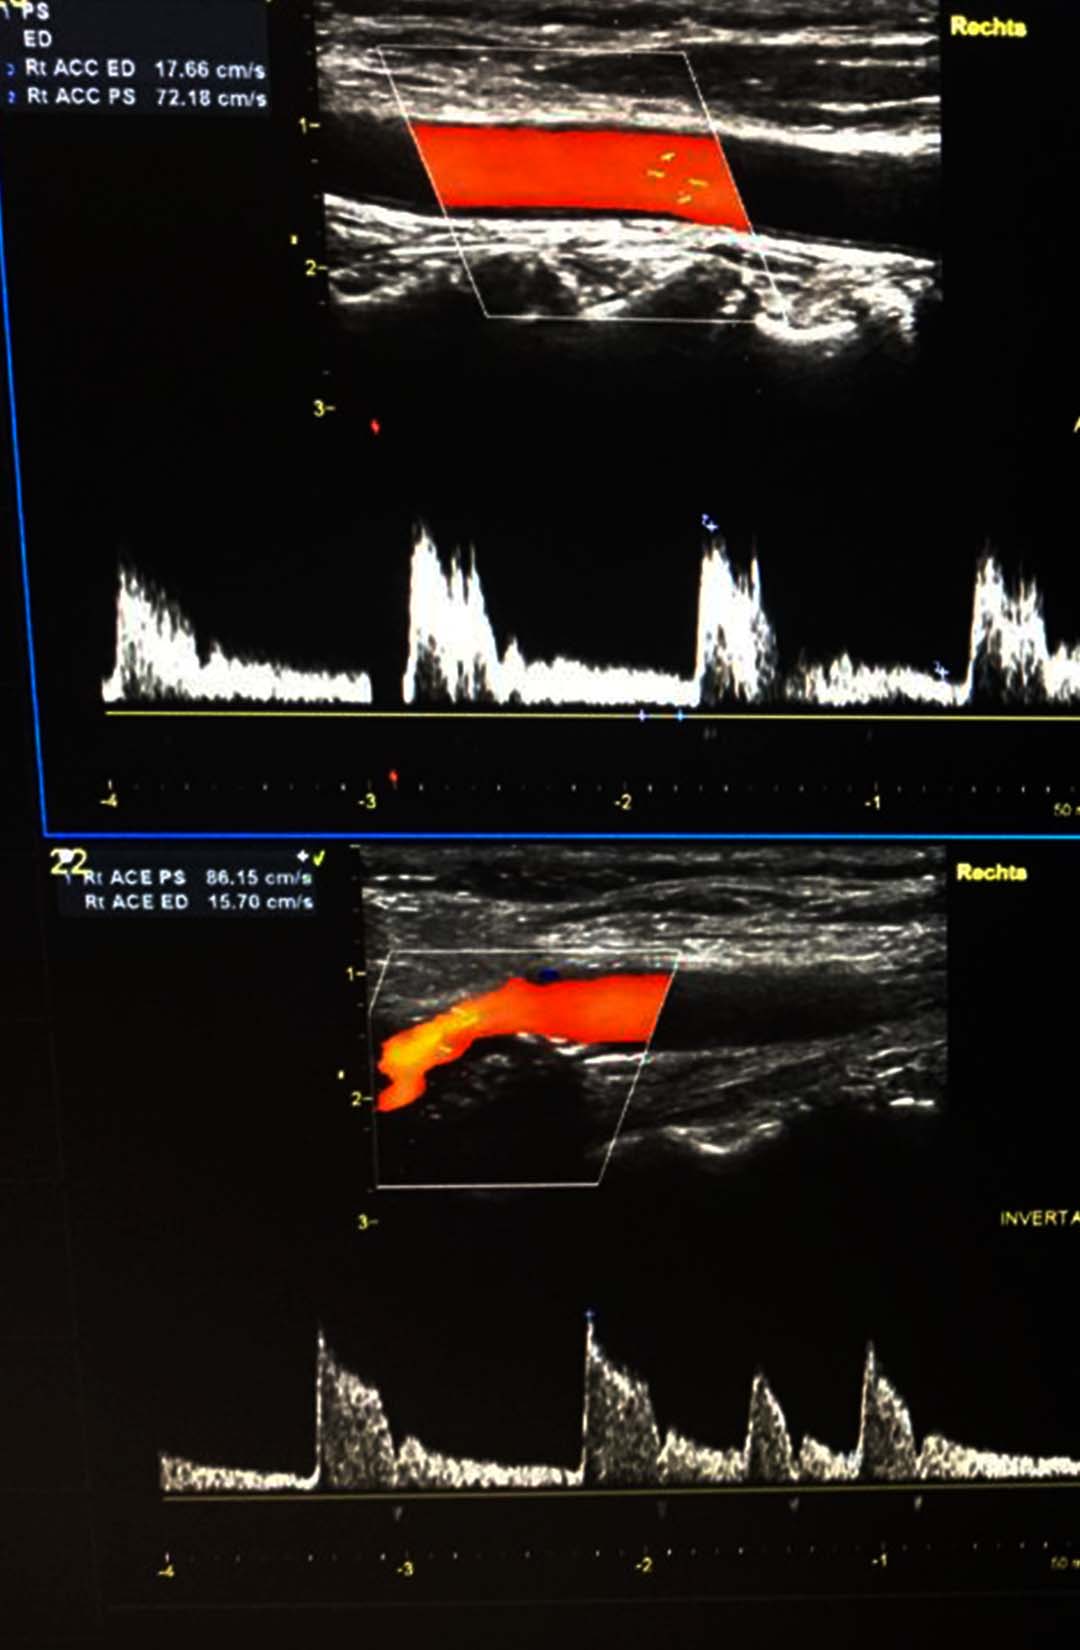

Carotisduplex-Sonografie untersucht die hirnversorgenden Halsgefäße (Carotiden und die Vertebralarterien). Die Verkalkungen der Arterien (Arteriosklerosen) können diagnostiziert werden, weiteres kann eine Verdickung der Gefäßwand (Intima-Media-Dicke) bestimmt werden. Dadurch kann eine prognostisch gute Einschätzung der Herz-und Gehirn-Infarktrisiken sowie der Herz-Kreislaufrisiken erfolgen.

Die Patienten mit einer Arteriosklerose der großen Schlagadern gehören zur Risikogruppe für einen Herzinfarkt.

Die Prävalenz (Anteil der erkrankten Personen an der Gesamtpopulation) einer ≥50%igen Carotisstenose liegt bei Erwachsenen bei ca. 4%, ab dem 65. Lebensjahr steigt die Prävalenz auf 6-15% an.

Insgesamt werden ca. 15% aller zerebralen Ischämien durch Stenosen oder Verschlüsse der extracraniellen A. carotis verursacht.